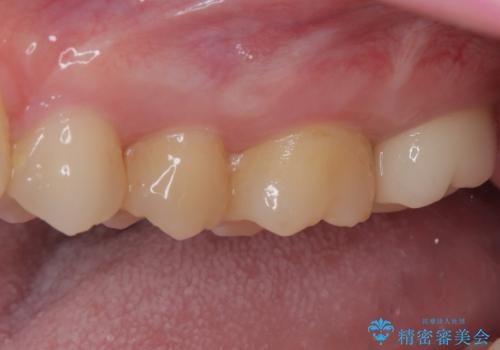

奥歯のむし歯が痛い セラミックによるむし歯治療

- 奥歯に激痛が走り近医を受診したところ、根管治療が必要とのことで、当院での治療を希望して来院された患者様です。

奥歯2歯の間からむし歯が広がったようで、最後方歯は既に神経が失活している状態で、手前の歯は神経組織に問題はないものの速やかに処置が必要な状態でした。

最後方歯は根管治療を行った上でオールセラミッククラウンにて補綴治療を行うこととし、手前の歯はセラミックインレーにて修復治療を行うこととしました。